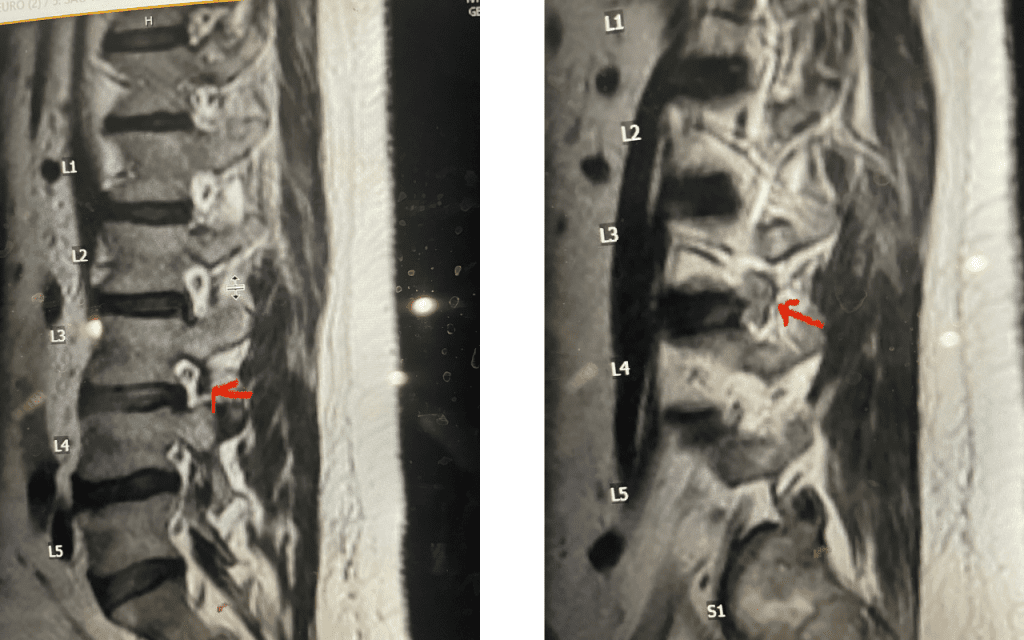

Fig 6: Axial T2-weighted lumbar MRI revealing a large extraforaminal disc herniation with severe compression of the left L3 nerve (red arrow).

Fig 7: Sagittal T2-weighted lumbar MRI with side by side comparison of the normal open right L3-4 foramen (red arrow) compared to the left L3-4 foramen filled with a large disc fragment (red arrow).

Here is a case of an extraforaminal disc fragment causing severe pain and weakness: This 60-year-old male presented with severe anterior thigh pain, numbness, and weakness for 3 weeks. He had failed epidural steroid injections. His left leg buckled when he walked. Imaging revealed a massive left L3-4 extraforaminal disc herniation, beyond the facet (Fig 6). This was severely compressing the left L3 nerve root in the L3-4 foramen (Fig 7). It was felt that the patient required surgery, as he would not be able to participate in physical therapy and had a neurological deficit. We performed an extraforaminal approach and removed a massive disc fragment that was revealed as the intertransverse membrane was reflected from the L4 transverse process-facet junction. We were able to visualize the L3 spinal root exiting above that had been compressed by the large fragment we removed (Fig 8). The patient post-op had a dramatic improvement neurologically and with significantly improved pain in his leg.